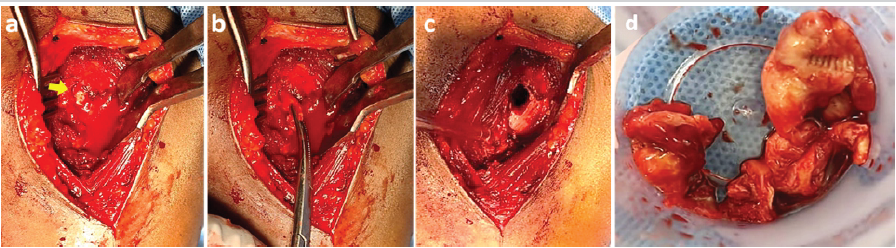

An excision biopsy followed by extended curettage was performed. A cortical window was created to gain access to the lesion, which was found to be filled with a yellow-colored mass (Fig. 2).

Figure 2: Intraoperative photographs demonstrating (a) fatty extrusion of the lesion through the proximal humerus, (b) extraction of the lesion, (c) the resultant cavity following its removal, and (d) the gross appearance of the excised lesion.

Contrast was injected to delineate the boundaries of the lesion, and the mass was excised in toto. Gross examination revealed a soft yellow mass with multiple septations enclosed within a thin capsule. Complete excision was confirmed using fluoroscopy. Extended curettage was performed using hydrogen peroxide. The resultant cavity was filled using bioabsorbable antibiotic-impregnated polymethylmethacrylate beads along with autologous bone graft harvested from the ipsilateral iliac crest (Fig. 3).